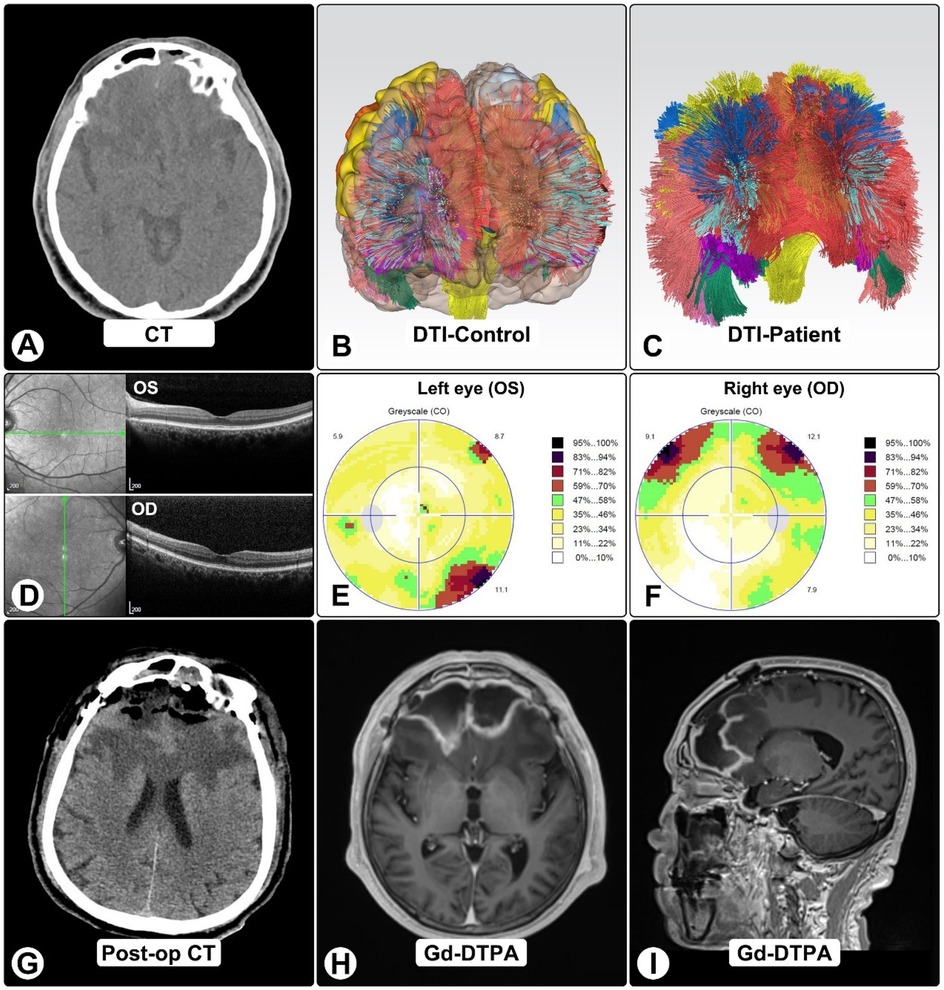

Four months after craniotomy, stereotactic biopsy confirmed A. fumigatus by NGS; serum GM and β-D-glucan were now positive. Sinonasal biopsies demonstrated invasive hyphae. DTI tractography showed marked frontal tract loss (Figures 3B,C). OCT was normal, while visual fields showed dense bilateral defects consistent with compressive optic neuropathy (Figures 3D–F).

Panel of medical images: A shows a CT brain scan. B displays a diffusion tensor imaging (DTI) scan of a control subject's brain. C presents a DTI scan of a patient's brain. D depicts optical coherence tomography (OCT) images of both eyes. E and F are visual field maps for the left and right eyes, respectively. G shows a post-operative CT brain scan. H and I feature gadolinium-enhanced MRI images, with H an axial view and I a sagittal view.

Figure 3. DTI tractography, OCT, and visual findings. (A) Pre-op CT shows bilateral frontal lesions with vasogenic edema and mass effect. (B,C) DTI tractography in normal brain (B) and patient (C), showing marked frontal tract loss, including bilateral anterior thalamic radiations, genu of corpus callosum, cingulum bundles, and forceps minor. (D) OCT imaging. (E,F) Octopus visual fields show right superior altitudinal defect (E) and left inferotemporal scotoma (F), consistent with compressive optic neuropathy. (G) Post-op CT showing expected changes after craniotomy and abscess evacuation. (H,I) One-month post-op MRI shows residual ring-enhancing lesions with reduced size and mass effect.

Multidisciplinary management with CNS-penetrant azoles (voriconazole and isavuconazole), blood-pressure control, and supportive care led to steady improvement. One-month MRI showed smaller lesions and reduced mass effect (Figures 3H,I). At six months, he was independent in daily activities with mild residual cognitive impairment and persistent visual-field loss (Figure 4).